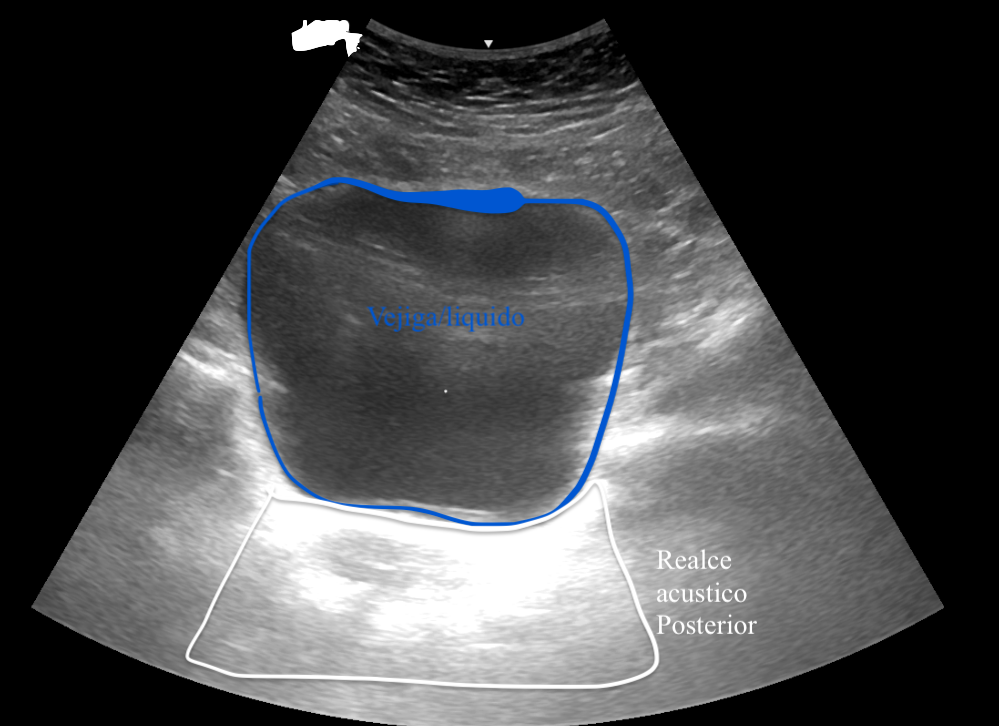

Vejiga con refuerzo acústico posterior en corte suprapúbico

Corte suprapúbico de vejiga mostrando refuerzo acústico posterior característico

2. Refuerzo Posterior

El refuerzo posteriorÁrea brillante detrás de estructuras llenas de líquido es un artefacto que ocurre cuando las ondas ultrasónicas atraviesan una estructura llena de líquido. Este fenómeno se observa frecuentemente en estructuras como quistes o la vejiga, donde los líquidos, al tener menor atenuación que los tejidos sólidos, permiten un mayor paso de las ondas ultrasónicas, resultando en un área más brillante o "refuerzo" posterior a la estructura.

Relevancia Clínica

• Facilita la diferenciación entre estructuras quísticas y masas sólidas

• Permite identificar estructuras anatómicas con contenido líquido

• Ayuda en el diagnóstico diferencial de lesiones benignas

• Crucial para la evaluación de estructuras como vejiga, quistes ováricos y hepáticos

Importancia Diagnóstica

Este artefacto es fundamental para:

• El diagnóstico diferencial entre masas quísticas y sólidas

• La evaluación de estructuras anatómicas con contenido líquido

• La identificación de lesiones sin interfases internas detectables

• La caracterización de tejidos en zonas fibrosas